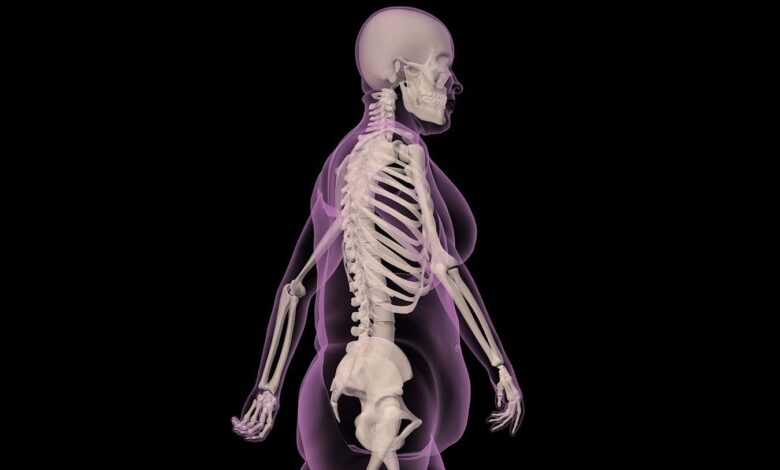

Постоји, наравно, озбиљна мана превише телесне масти. Превише добро знамо да је гојазност повезана са бројним здравственим стањима, укључујући рак, кардиоваскуларне болести и дијабетес типа 2. Упркос томе, многи људи који су гојазни не доживљавају ове штетне ефекте, што је знак да се дешава нешто сложеније. Испоставило се да је маст далеко од пасивне, као што извештавамо у нашој насловној причи на страни 28. Уместо тога, то је виталан, динамичан део тела, орган сам по себи који ради са мозгом, костима и другим стварима како би нам помогао да останемо здрави.

Ово радикално преобликовање масти помаже нам да боље разумемо гојазност – не као морални неуспех, већ као отказ органа. То може померити нарацију од срамоте и окривљавања ка развоју бољих третмана за то стање. Заиста, напори се сада усмеравају ка новим начинима да се „репрограмирају“ масне ћелије које не функционишу како би се обновило здравље и можда чак трансформисала „нездрава“ гојазност у бенигнији облик.

Масноћа је виталан, динамичан део тела, сам по себи орган који ради на одржавању здравља

Охрабрујуће, ово можда неће захтевати драматичан губитак тежине. Чини се да многе предности данашњих лекова за мршављење не потичу из килограма које помажу да се скину, већ пре из побољшања дистрибуције масти и функције.

Постизање ове трансформације било би револуционарно, не само у побољшању здравља, већ иу преобличавању како изгледају здрави облици тела. Једна лоша страна безначајног успеха ГЛП-1 лекова је тај што ризикују да смање покрет позитивности на масноћу и поново подстакну старе моралне судове о величини тела и самоконтроли.

Али када би се масноћа могла репрограмирати, много више нас би могло живети дуже, здравије без опседнутости својом величином. Боље разумевање биологије масти и начина на који она комуницира са остатком тела је добро место за почетак.